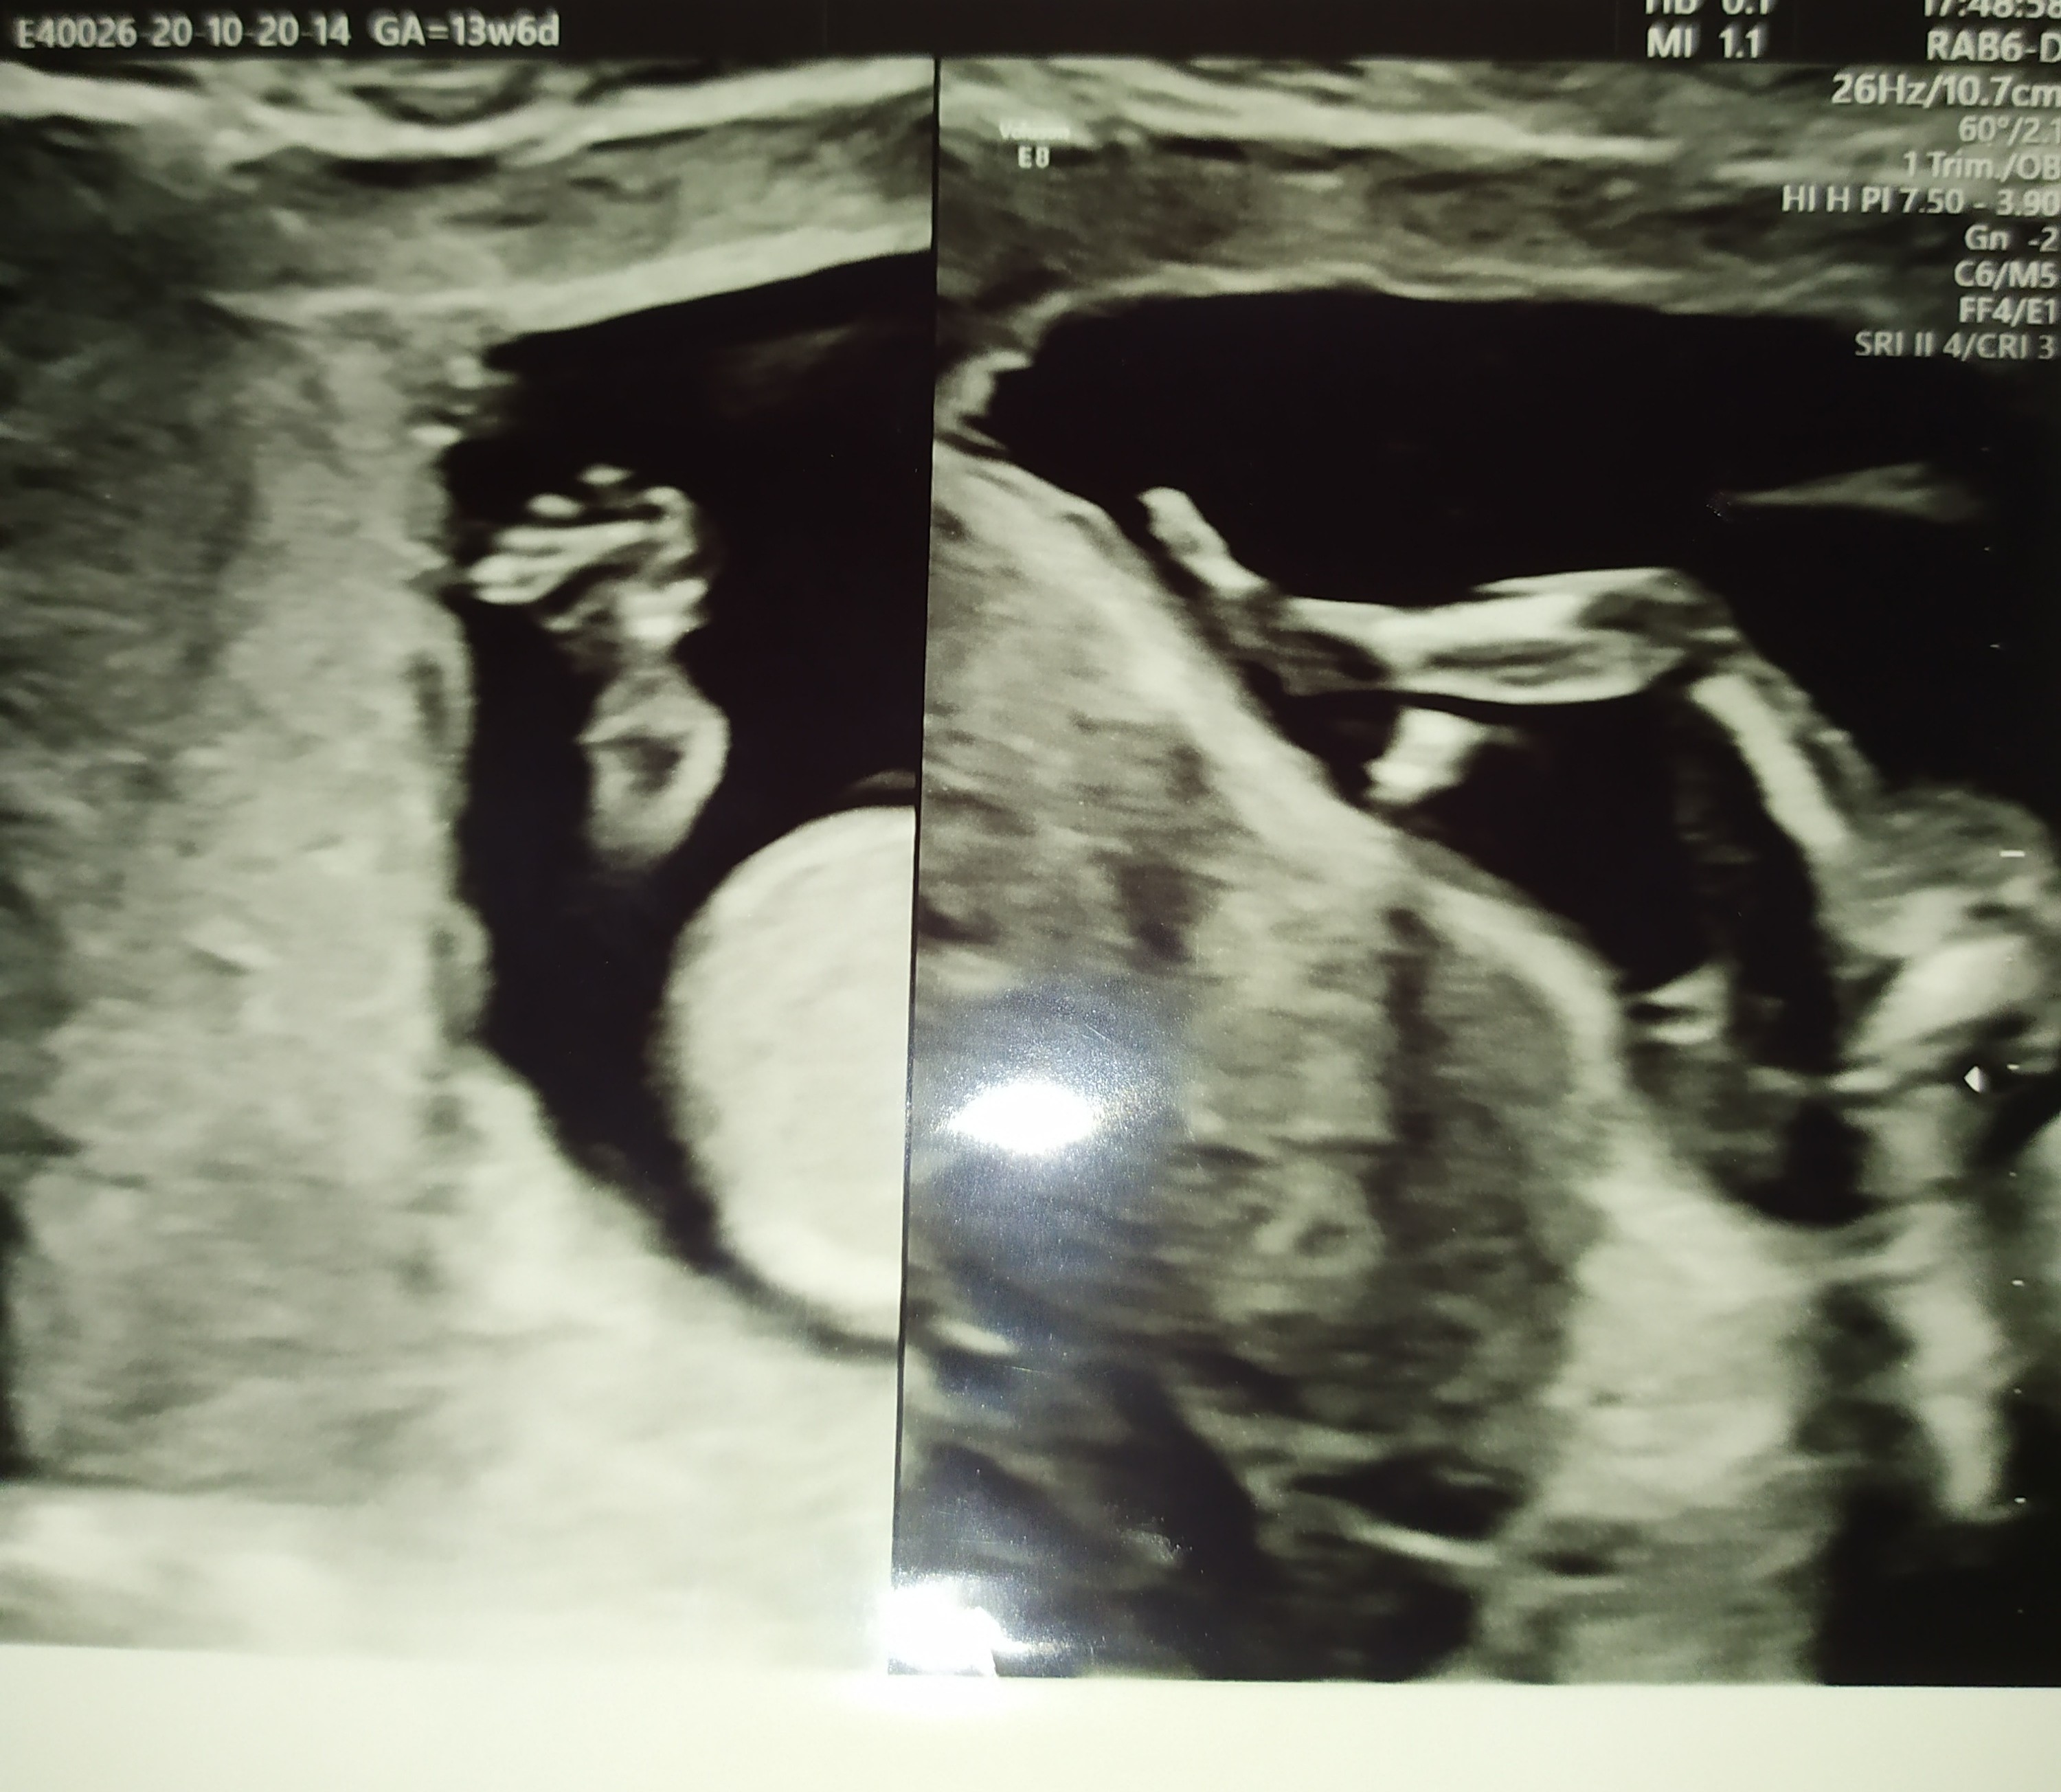

Z przyjemniejszych rzeczy dzidzia coraz bardziej daje znać o sobie